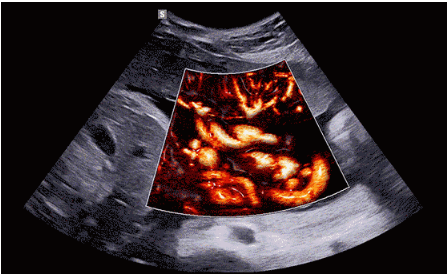

CrystalLive?是三星最新的超聲成像引擎,同時增強了2D圖像處理能力、3D渲染能力和彩色信號處理能力,能夠在復(fù)雜情況下提供出色的圖像性能,具備檢測外周血管、微循環(huán)血流的能力。